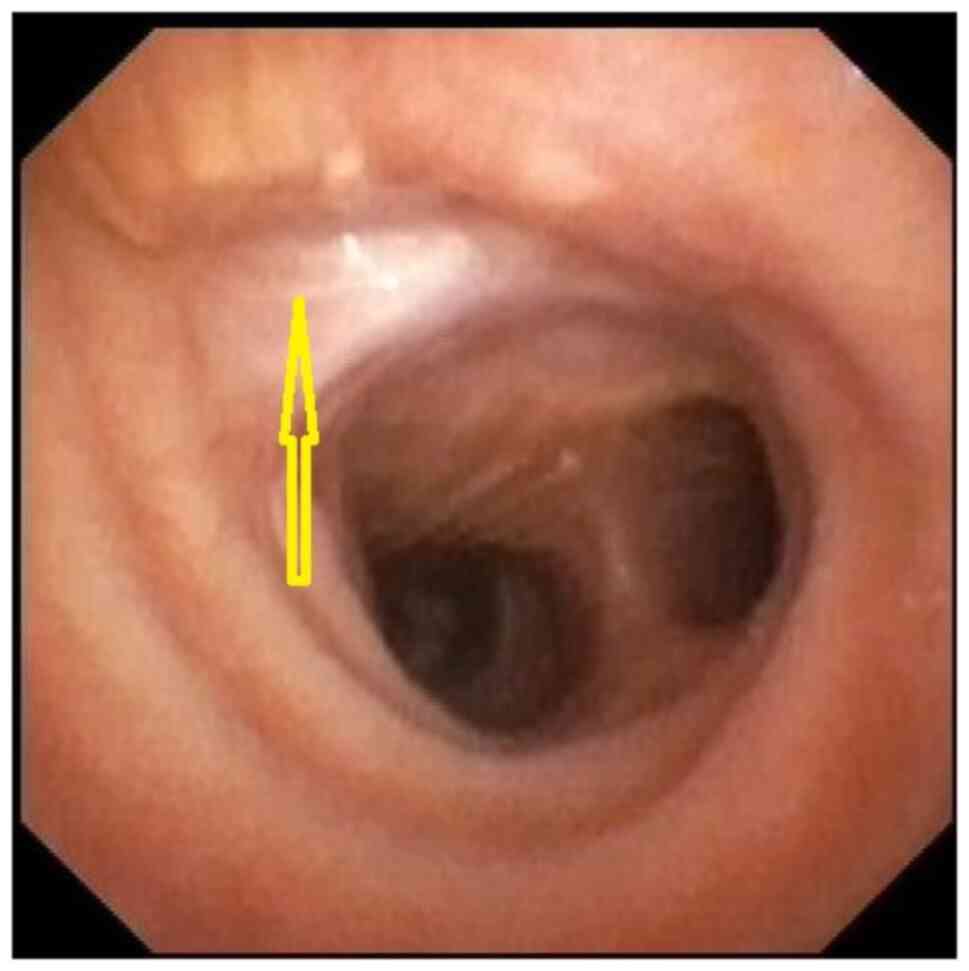

Acquired benign trachea‑oesophageal fistula is a rare benign pathological entity with varying aetiologies that most often occurs post‑intubation. This case report presents the case of a female patient, 31 years old, admitted to the emergency room with sepsis syndrome following bilateral aspiration pneumonia caused by a large trachea‑oesophageal fistula. The fistula was the result of intra‑tracheal migration of an oesophageal stent placed for post lye ingestion stenosis. Esophageal diversion and partial resection with oesophageal patch to repair the tracheal defect, under general anaesthesia with ventilation using rigid bronchoscopy and high frequency jet ventilation (HFJV), followed at a later date by esophageal replacement with colic graft were the procedures performed with a view to curing the patient. In conclusion, complex cases always require a tailored approach. It is important to note that HFJV may be applied for a longer period of time and the oesophagus can be used as patch for the posterior tracheal wall in selected cases. Staged surgery is also an option when the patients' poor health status does not permit major surgery.

Figure 2